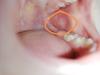

Доброе утро. Посмотрите фото, пожалуйста. Это стоматит у ребёнка?

Афтозный стоматит? Похоже. У нас по 1, 2 шт вылазило у младшей, закладывала мазь асепта. Просто потому что дома для старшей есть эта мазь. А так смотрела в интернете)

@milankaburova нам год,у нас сейчас афтозный стоматит,да,примерно так и выглядит он,мы с этим поехали к педиатру,назначили холисал и кондид беби,ну и ромашку пить

Похоже. Но так же это может быть обострение герпеса 6 типа(нам так в поликлинике сказали). Холисал мазать. У старшего эта проблема с рождения🥺

Спасибо девочки. Обошлось у нас. Дочь щеку прикусила просто.